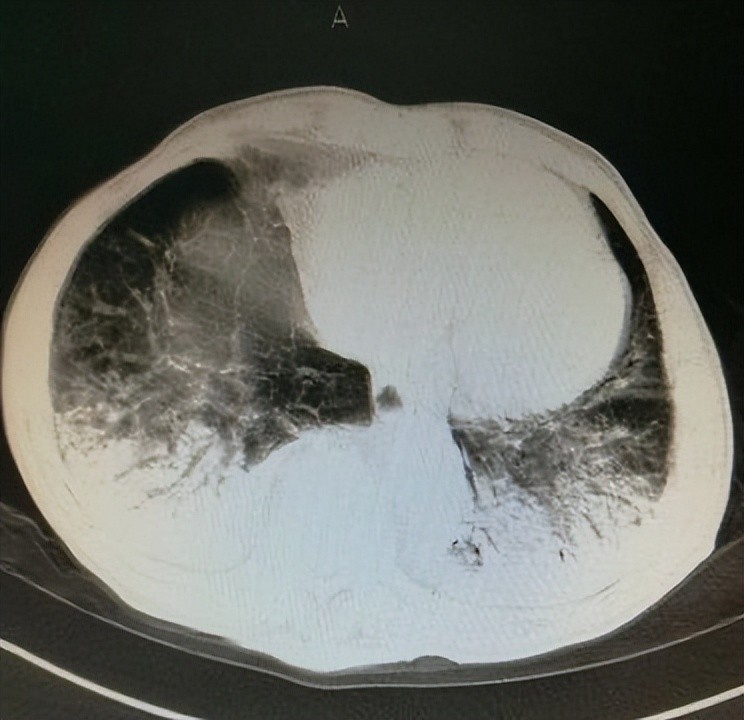

不到48小时,小女孩就因为广泛性肺纤维化陷入昏迷。最后,这朵未绽放的花骨朵,就这么凋零了。

最可怕的是肺纤维化。简单说就是肺部失去功能,没法跟外界交换氧气了。也就是说,人是被活活憋死的。

从喝下去到死亡,长则十来天,短则一两天,期间那种痛苦,让很多人觉得死亡反而是种解脱。

偏偏百草枯还没有解药,造成的损伤都是不可逆的。这就是为什么它被称为"第一毒药",致死率高达90%以上。